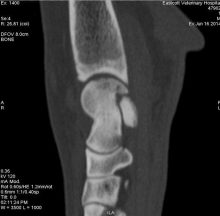

Hock Fracture Repair in Dog with Osteochondritis Dissecans

Repair of hock fracture secondary to osteochondritis dissecans of the medial talar ridge This hock fracture was secondary to ...